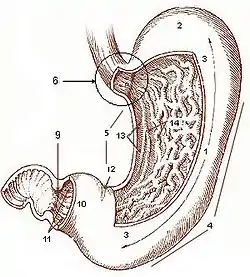

Gross Anatomy

1. Body of stomach 2. Fundus 3. Anterior wall 4. Greater curvature 5. Lesser curvature 6. Cardia 9. Pyloric sphincter 10. Pyloric antrum 11. Pyloric canal 12. Angular notch 13. Gastric Canal 14. Rugal folds

Food enters the stomach from the esophagus at the at the cardia and passes into the stomach. In the fasting state the stomach is kept in a state of contraction, but the presence of food causes it to expand. The rugae of the stomach are folds in the mucosa seen in the fasting state; unlike the small intestine they are not there to increase surface area for absorption. Numerous pores are seen: the openings to the gastric glands which secrete enzyme pepsinogen and hydrocloric acid as well as mucous. The hydrochloric acid produces a pH of about 2. This highly acidic environment serves two purposes: first, to provide an environment hostile to bacteria and other pathogens; second, to denature protein and cause it to unfold, thereby increasing the area that pepsins can attack (see Digestion below)

The stomach is divided into three parts: the fundus, the main body, and the pyloric antrum. Stored food is mixed with enzymes and HCl to form chyme. The muscles feed the chyme down to the pyloric antrum, where it is thoroughly mixed, and fed in small amounts into the small intestine by relaxation of the pyloric valve.

The arterial supply to the stomach is from the coeliac artery.

The venous drainage of the stomach drains into the venous portal system

Microscopic Anatomy

The basic layout pattern holds true in the stomach, although the stomach has a third inner layer of oblique muscle fibers. The mucosal layer has numerous pits opening into the lumen, the mouths of the gastric glands. Some of these glands penetrate down into the submucosal layer.